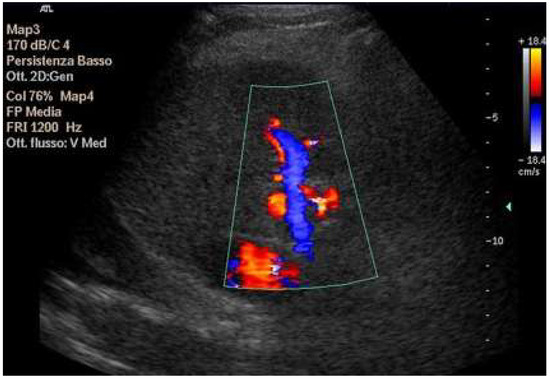

Abdominal ultrasound is a fundamental diagnostic tool in clinical practice, due to its availability, safety, and overall accuracy. This Special Issue will delve into the most recent technological and methodological innovations in abdominal ultrasound imaging, offering readers a comprehensive overview of advanced techniques, specific clinical indications, and solutions to emerging challenges. Among the various topics, it will cover the use of high-resolution probes, the integration of elastography for assessing liver fibrosis, and the application of contrast-enhanced ultrasound for identifying complex lesions. Strategies for training and professional development will also be examined to improve ultrasound performance and result interpretation.

- doppler